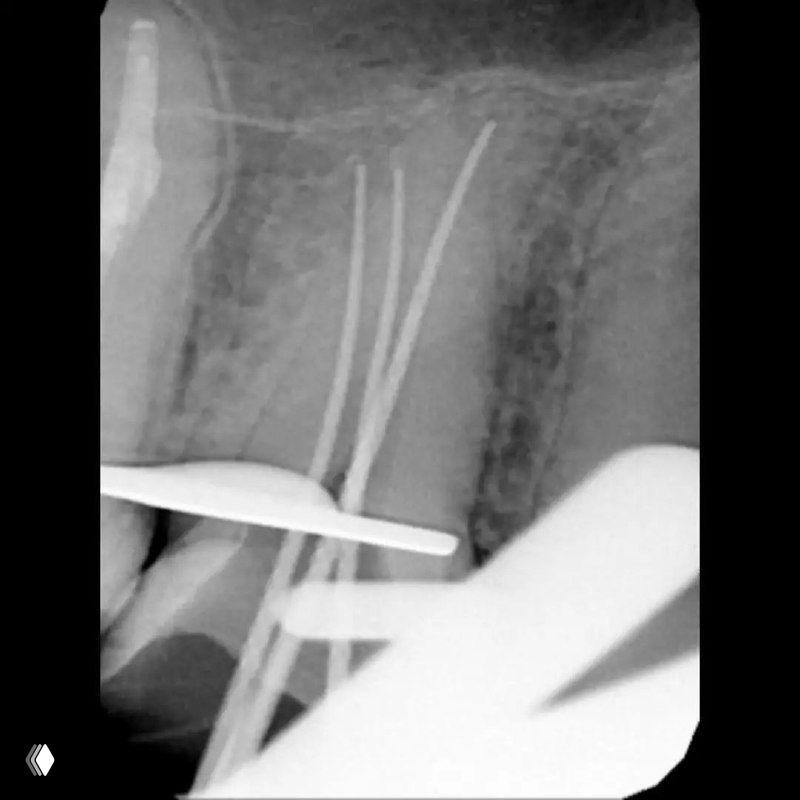

Распространенность: 1 премоляр вч - 3.2%, 2 премоляр вч - 0.4%

На что обратить внимание:

- классическую овальную полость доступа нужно немного расширить в области щёчных каналов в мезио-дистальном направлении

- проводить аккуратное расширение щёчных каналов, так как в области данных корней очень мало дентина (в моём случае расширение 25.04)

- аккуратно латералить без лишнего давления, а для вертикалки использовать самые тонкие плаггеры. А в идеале сделать гибрид.